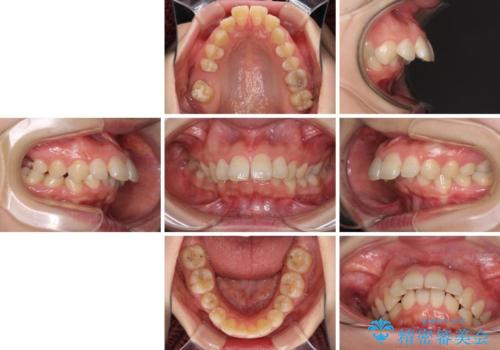

飛び出した前歯 抜歯矯正で横顔が劇的変化

- 飛び出した上顎前歯を気にして来院された患者様です。

下顎は左右2番目の歯が2本欠損しており、上下前歯の前後的な位置は著しくずれている状態でした。

骨格的にも上顎骨が前突傾向にあり、極端な過蓋咬合になっていました。

強い咬合力に抵抗するように歯を動かす必要があるにもかかわらず、上顎第一大臼歯が1本欠損しているため、治療は困難を極めることが予想されました。

上顎前突を改善するために上顎左右第一小臼歯を抜歯し、補助装置を用いて上顎臼歯が前方に移動しないように工夫しながら、表側のワイヤー装置にて歯列を整えていくこととしました。